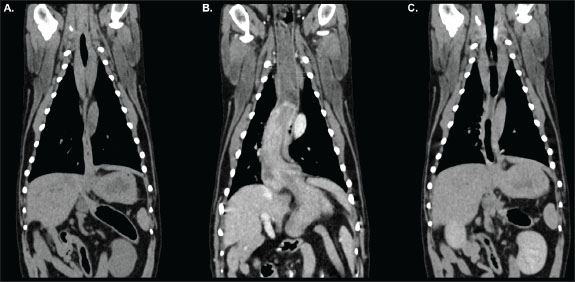

Pre-contrast acquisitions demonstrated a normally positioned stomach; however, the gastric fundus was cranially herniated through the oesophageal hiatus into the caudal esophageal lumen on the venous-phase post-contrast scan (Figs. 1 and 2). The distal oesophageal wall encircled part of the gastric fundus, creating a target-like appearance on transverse-plane images (Fig. 3). The orad oesophagus contained a small-to-moderate amount of heterogeneous fluid-to-soft-tissue-attenuating material. Delayed post-contrast images showed the stomach had returned to its normal anatomical position.

Fig. 2. Dorsal reconstructions of the thorax and cranial abdomen acquired during pre-contrast (A), venous-phase (B), and delayed post-contrast (C) phases of the study. The stomach is appropriately positioned with minimal distension of the oesophagus in the pre-contrast (A) and delayed (C) acquisitions. Gastroesophageal intussusception is identified during the venous-phase acquisition (B) as outlined in Figure 1.

Fig. 3. Transverse-plane images of the thorax from the venous-phase acquisition at approximately the level of the T4 (A), T5 (B), T8 (C), T9 (D), and T10 (E) vertebrae. The gastric fundus (green arrow) has herniated cranially through the oesophageal hiatus into the caudal thoracic oesophagus (red arrow). Note that unlike in cases of hiatal herniation, the distal oesophageal walls are visualised surrounding part of the gastric fundus, creating a target-like appearance, indicative of intussusception.